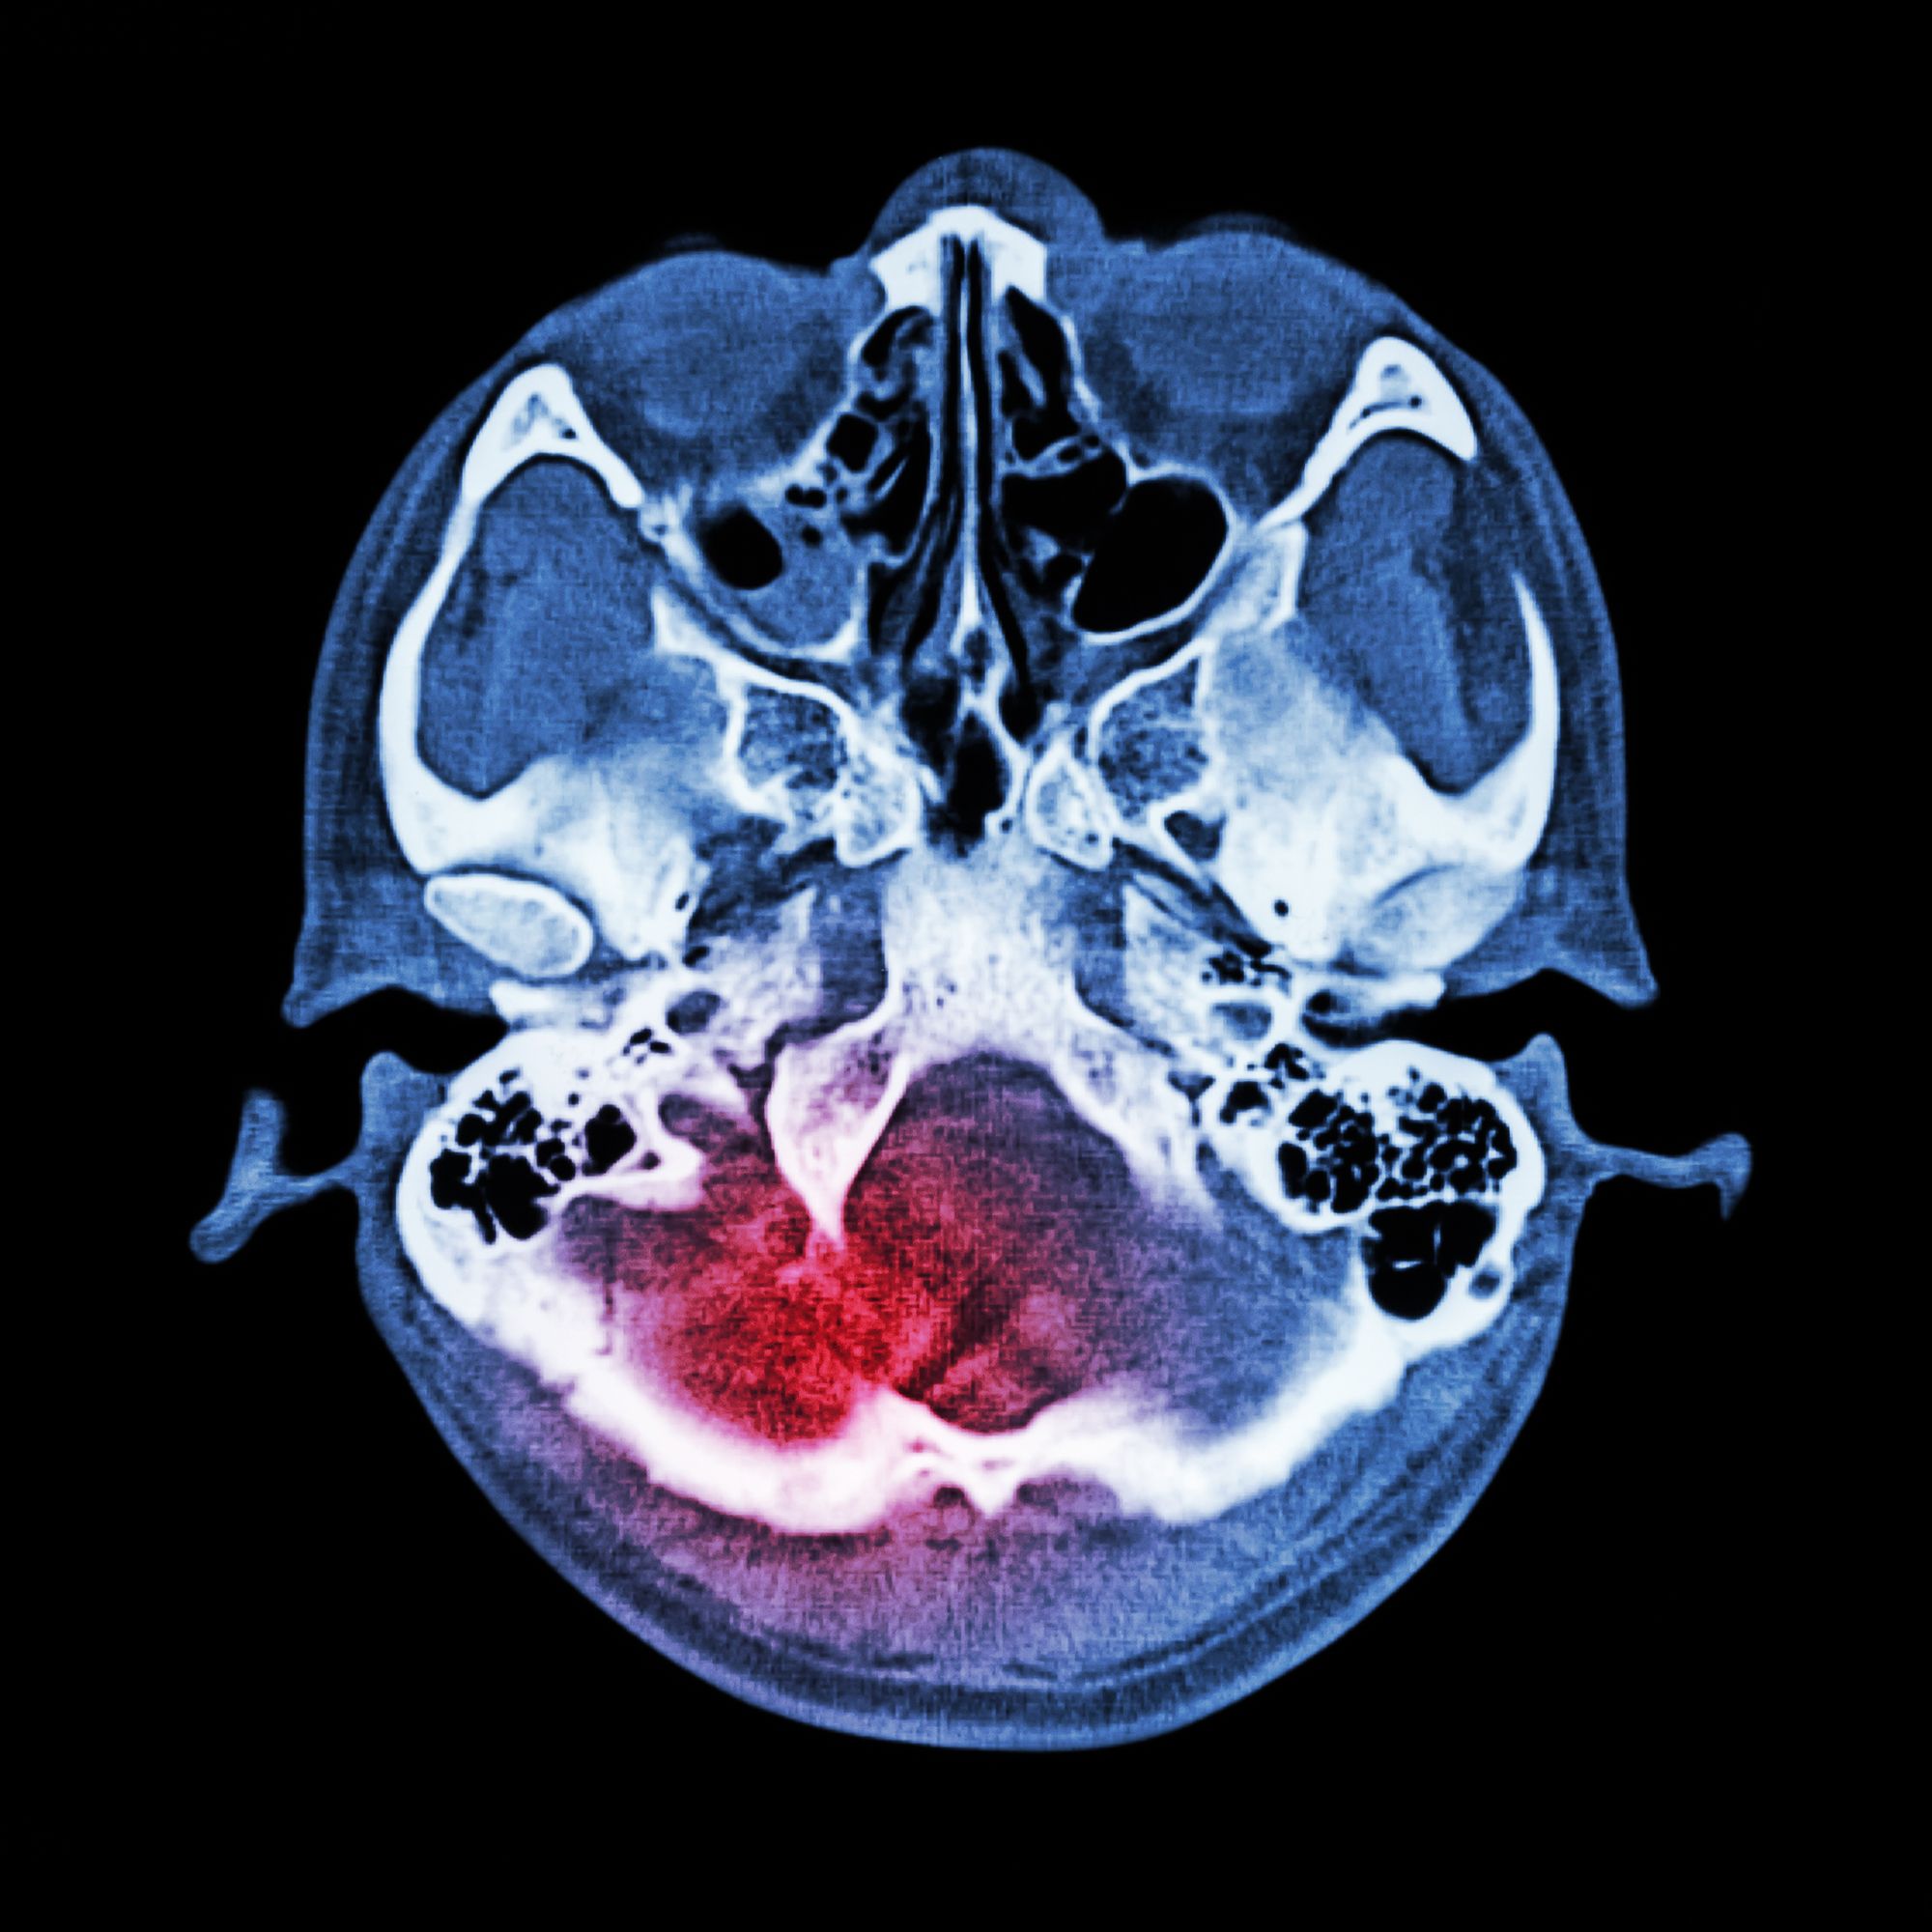

However, after its use and as an alleged direct result, George suffered a hemorrhagic stroke in May and a “life-threatening, irreversible bleed from the use of Xarelto, as well as severe pain and suffering,” the Xarelto lawsuit explains.